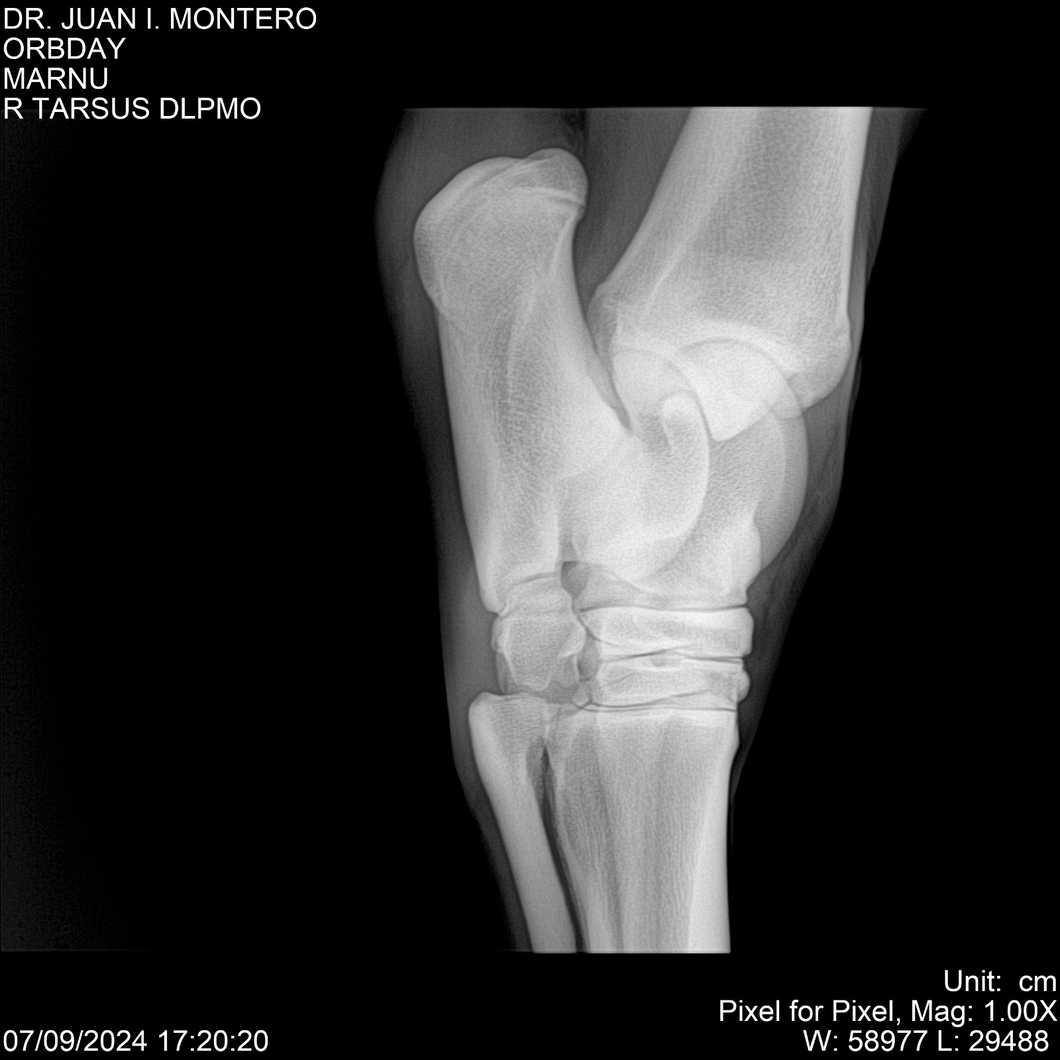

• Empresa: Abelenda N. R., Walter Hugo